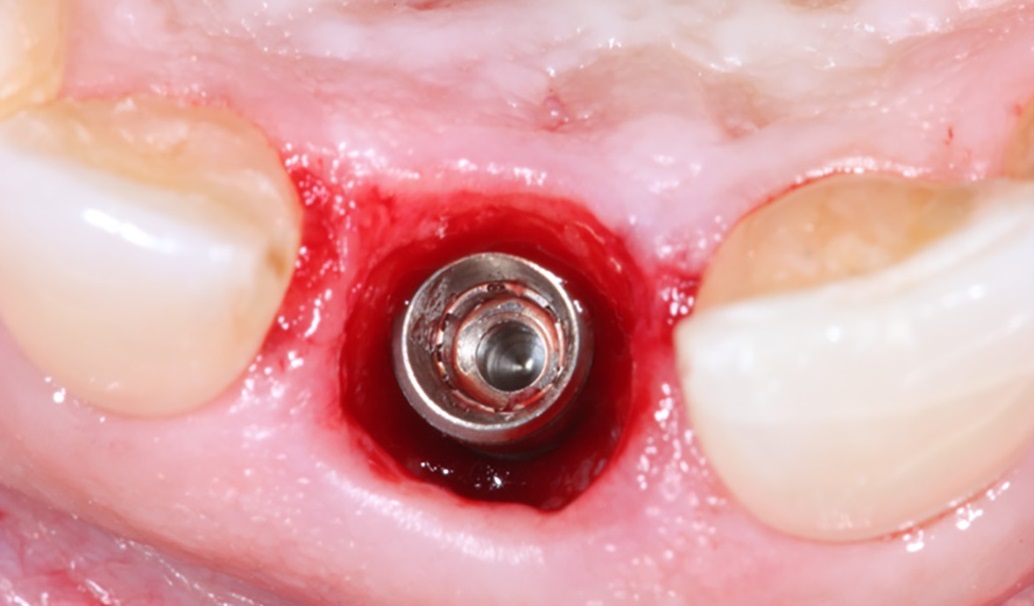

Bước 2: Đặt trụ lành thương cá nhân hóa để tạo hình mô nha chu.

Trụ lành thương cá nhân hóa sẽ được đặt luôn trong thì đặt trụ. Trong một số trường hợp xương hàm thiếu hổng hoặc lợi không đủ thể tích, Healing Customized có thể được đặt sau 2 tháng, sau khi trụ implant đã tích hợp.

trồng răng implant cá nhân hóa

• Bước 3: Đặt trụ lành thương cá nhân hóa.

Trụ lành thương cá nhân hóa có thể được đặt ngay sau khi đặt trụ (đa phần là vậy) hoặc đặt ở thì hai, sau khi implant đã ổn định, nếu phải đặt ở thì 2, thì bạn cần tới nha khoa thêm một lần hẹn nữa, cách lần hẹn đặt trụ từ 2 tới 4 tháng tùy loại trụ.

Đa phần các trường hợp sẽ được đặt trụ lành thương trong thì đặt trụ implant, đây cũng là một ưu điểm của giải pháp, giúp bạn không cần phẫu thuật quá nhiều lần.

trồng răng implant cá nhân hóaMột trường hợp nhổ răng, cấy trụ implant bằng guideline và đặt trụ lành thương các nhân hóa bằng titanium, tất cả trong một lần phẫu thuật.